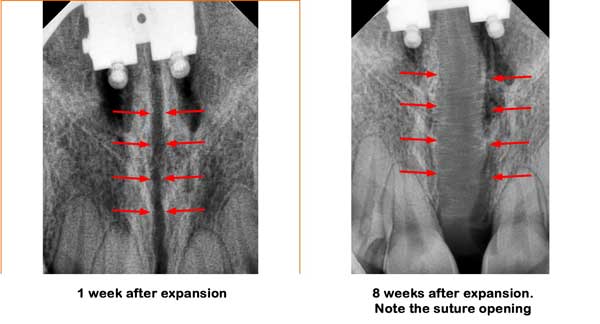

Notice the above sequence of changes in her upper jaw width. The X-rays below also show her expansion and suture opening after stage one and after stage two.

This patient has been on allergy medications for years to improve their breathing. However, after watching Dr. Kanaan with Debra Duncan talking about MARPE and its benefits, he decided to undergo the MARPE procedure. Dr. Kanaan placed the MARPE with longer screws to maximize its force. His case was a complete success with over 5 mm of expansion in his basal nose level. Patient was pleased with his MARPE treatment in Houston.

Notice the excellent expansion on the X-ray and how it was filled with bone.